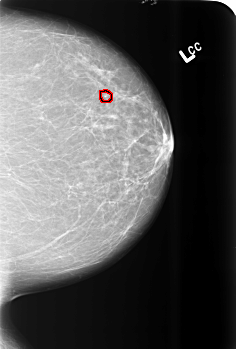

B_3473_1.LEFT_CC

LEFT_CC LINES 5576 PIXELS_PER_LINE 3768 BITS_PER_PIXEL 12 RESOLUTION 50 OVERLAY

FILE: B_3473_1.LEFT_CC.OVERLAY

TOTAL_ABNORMALITIES 1

ABNORMALITY 1

LESION_TYPE CALCIFICATION TYPE PLEOMORPHIC DISTRIBUTION CLUSTERED

ASSESSMENT 4

SUBTLETY 4

PATHOLOGY BENIGN

TOTAL_OUTLINES 1

BOUNDARY